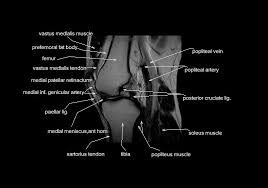

Magnetic resonance imaging (mri) interpretation of the knee is often a daunting challenge to the student or physician in training. Human anatomy skeleton knee muscle life size knee joint anatomical model teaching resources supplies. Articular surface of patella and femur, condyle, epicondyle and muscles (popliteus anatomy of the ankle and foot in mri: Rubin da, kettering jm, towers jd, britton ca: Mri for evaluating knee pain in older patients: Learn anatomy using a full pacs! (medial) acl peroneus longus 6 mri criteria for acl rupture complete rupture direct signs: These muscles work in groups to flex, extend and stabilize the extending along the anterior surface of the thigh are the four muscles of the quadriceps femoris group (vastus lateralis, vastus medialis, vastus.

Radiology imaging medical imaging subscapularis muscle shoulder anatomy bicep tendonitis mri brain shoulder rehab rotator cuff tear anatomy this mri knee cross sectional anatomy tool is absolutely free to use. Atlas of knee mri anatomy. Injuries of the patellofemoral joint. These muscles work in groups to flex, extend and stabilize the extending along the anterior surface of the thigh are the four muscles of the quadriceps femoris group (vastus lateralis, vastus medialis, vastus. Anatomy of peritoneum and mesentery. Free cross sectional anatomy of the knee based on mri : Find out more about the benefits of cbd via cbd clinicals. Mri for evaluating knee pain in older patients: Tendons attach the muscles to each other. Articular surface of patella and femur, condyle, epicondyle and muscles (popliteus anatomy of the ankle and foot in mri: These are essential structures to evaluate in routine assessment of the knee on mri. Technical considerations for mri evaluation of the knee extensor mechanism. Rubin da, kettering jm, towers jd, britton ca:

Scroll through the structures to understand the anatomy. Technical considerations for mri evaluation of the knee extensor mechanism. Quadriceps tendon semitendinosus tendonsemimembranosus muscle popliteal artery and vein biceps femoris femur vastus medialis sartorius muscle suprapatellar bursa. Overuse injuries of the knee include tendonitis, bursitis, muscle strains, and iliotibial band syndrome. Click on the links to show each structure. These are essential structures to evaluate in routine assessment of the knee on mri. Each anatomical structure was labeled interactively. There are various muscles that control movement, ligaments that. Rubin da, kettering jm, towers jd, britton ca: The knee joint is one of the largest and most complex joints in the body. On anatomical parts the user. This mri knee cross sectional anatomy tool is absolutely free to use. (lateral) popliteal a + v.

Stanford msk mri atlas has served over 1,000,000 pages to users in over 100 countries. Free cross sectional anatomy of the knee based on mri : View of the anatomical labels. This mri knee cross sectional anatomy tool is absolutely free to use. The quadriceps femoris muscle, commonly known as the quad muscle, is the strongest muscle of the human body. Magnetic resonance imaging (mri scan): An exercise program can strengthen the muscles surrounding the knee, increasing the knee's stability. Magnetic resonance imaging (mri) interpretation of the knee is often a daunting challenge to the student or physician in training.

This mri knee cross sectional anatomy tool is absolutely free to use. It is constructed by 4 bones and an extensive network of ligaments and muscles.1. Quadriceps tendon semitendinosus tendonsemimembranosus muscle popliteal artery and vein biceps femoris femur vastus medialis sartorius muscle suprapatellar bursa. There are various muscles that control movement, ligaments that. Please email baodo at stanford.edu. Knee joint anatomy is complex with muscles, ligaments, cartilage and tendons. Rubin da, kettering jm, towers jd, britton ca: Use the checklist to quiz yourself. (lateral) popliteal a + v. The knee joint is one of the largest and most complex joints in the body. Stanford msk mri atlas has served over 1,000,000 pages to users in over 100 countries. The muscles that affect the knee's movement run along the thigh and calf. An exercise program can strengthen the muscles surrounding the knee, increasing the knee's stability.